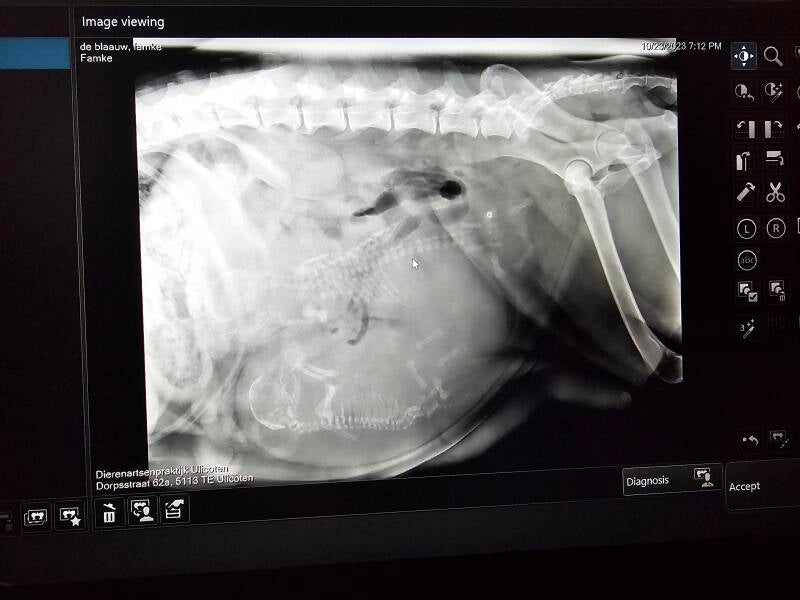

Bovenstaande foto is tijdens de bevalling gemaakt om er zeker van te zijn dat er geen pups achter zouden blijven, nog 2 werden er geboren de.laatste is overleden.